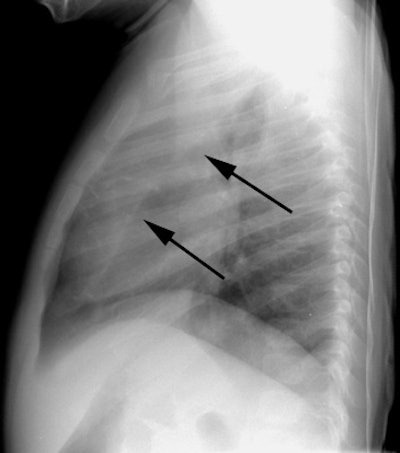

Left upper lobe collapse

The patient below presented with a history of reactive airways disease and shortness of breath. The frontal CXR demonstrated a vague opacity in the left upper lung that obscured the left upper mediastinal border and a segment of the left heart border. Note that the lateral edge of the opacity is ill-defined. The left hila was slightly uplifted. Lateral CXR demonstrated a retrosternal density (black arrows) representing the collapsed left upper lobe displaced anteriorly. |